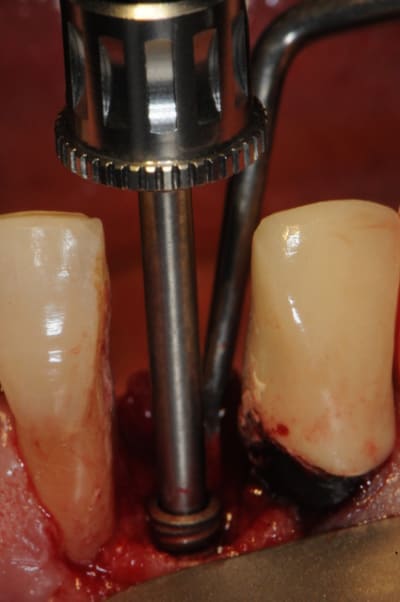

1)2) pilier impactable :ici c'est un 7° mais ils existent en 0, 7, 15 et 23°

3)4) essayage du pilier

5)6) essayage couronne provisoire

7) résine tab 2000

8) mise en place et durcissement

9) retrait de la provisoire et du pilier (il ne faut surtout pas appuyer trop fort sur ce dernier car sinon on risque de ne plus pouvoir le retirer avec la friction.

10)11) composite flow pour les finitions

12) couronne prête à être posée

13)14) impacteur et différents embouts (fonction de l'angulation du pilier)

15)16)17)18)19) jour zéro (dent en sous occlusion)